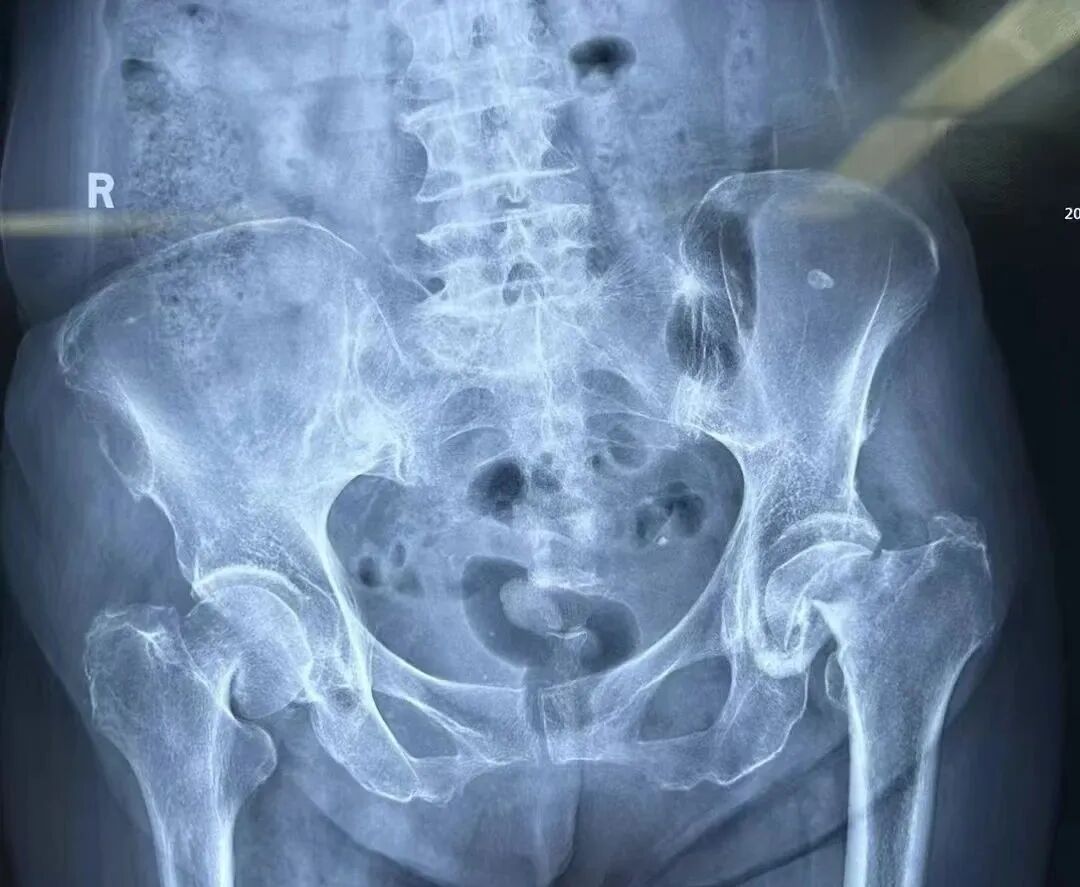

家住西影路的唐老太(化名)今年83岁,一个月内先后不慎摔倒了两次,结果导致左右两侧股骨颈均骨折,这使得她无法下地行走,就连翻身都极为困难。在家人陪同下来到陕西冶金医院骨科就诊。

考虑到老人年龄较大且左右两侧股骨颈均骨折,为避免二次手术带来的多重创伤,骨科主任赵学刚决定一次手术解决两侧问题。同期行双侧人工股骨头置换术,成功为她替换了双侧髋关节,手术过程十分顺利。术后第三天就能下地功能锻炼。老人和家属非常满意,对骨科医护人员精湛技术及悉心护理更是高度认可。出院后,特地为骨科送来了锦旗,以此表达诚挚谢意。